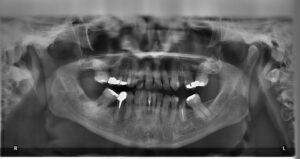

Kwik wordt al decennialang gebruikt in zogenaamde amalgaamvullingen — een legering van kwik met andere metalen zoals zilver, tin en koper. Deze vullingen waren jarenlang populair vanwege hun stevigheid en lange levensduur. Toch brengt het gebruik van kwik risico’s met zich mee voor zowel de gezondheid als het milieu.

Nederlandse tandartsen gebruiken tegenwoordig vrijwel uitsluitend composietvullingen — witte vullingen van kunsthars — die niet alleen veiliger zijn, maar ook esthetisch beter aansluiten bij de natuurlijke tandkleur. Deze moderne alternatieven bevatten geen schadelijke stoffen en zijn geschikt voor bijna alle soorten tandreparaties.